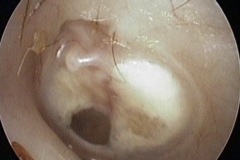

Perforation